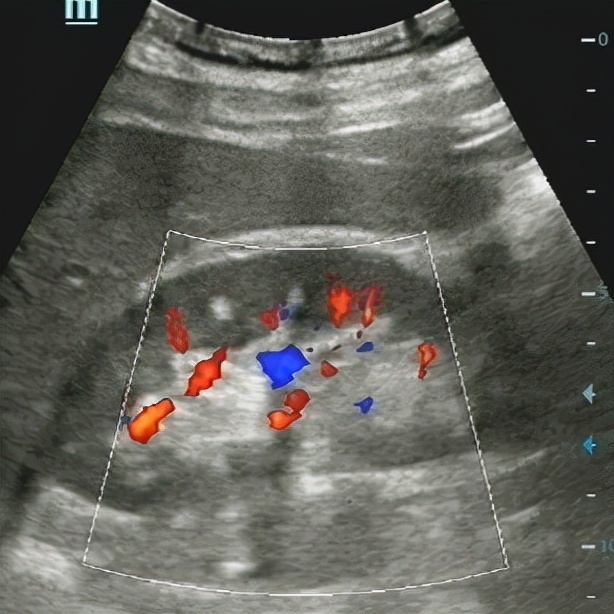

李四倒也听话,脱下裤子配合检查,我先尝试用线阵(浅表)探头经会阴看。

发现个小东西,约0.4x0.2cm,一上血流还有闪烁伪像。

放大深度,扩大扫查后,“嗯?居然还有个大的,大小约1.0x0.6cm”远场实在看不清,换凸阵(腹部)探头。